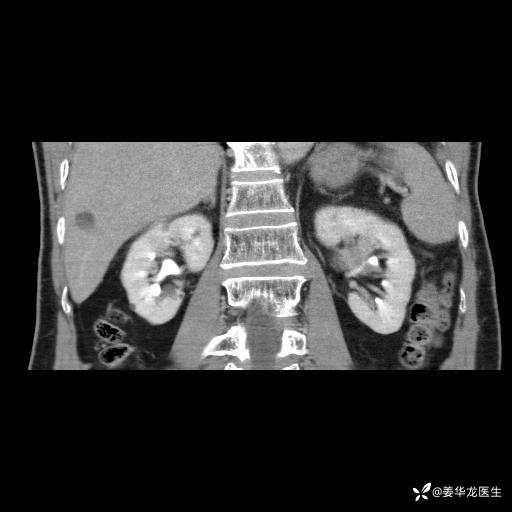

左肾中心型肾门部肿瘤39mm×34mm×36mm,右肾GFR25ml/min,部分切还是全切?

患者75岁老年男性,体重50kg,无高血压、肾病、糖尿病等基础病,检查发现左肾中心型肾门部肿瘤,右肾GFR只有25ml,无肉眼血尿,无镜下血尿。入院验血常规检查均正常,包括肾功能,肌酐102.7umol/L.

二、左肾肿瘤与左肾集合系、左肾动静脉关系密切,左肾部分切除术可行吗?成功率有多大?成功部分切后,肾功能还有多少?